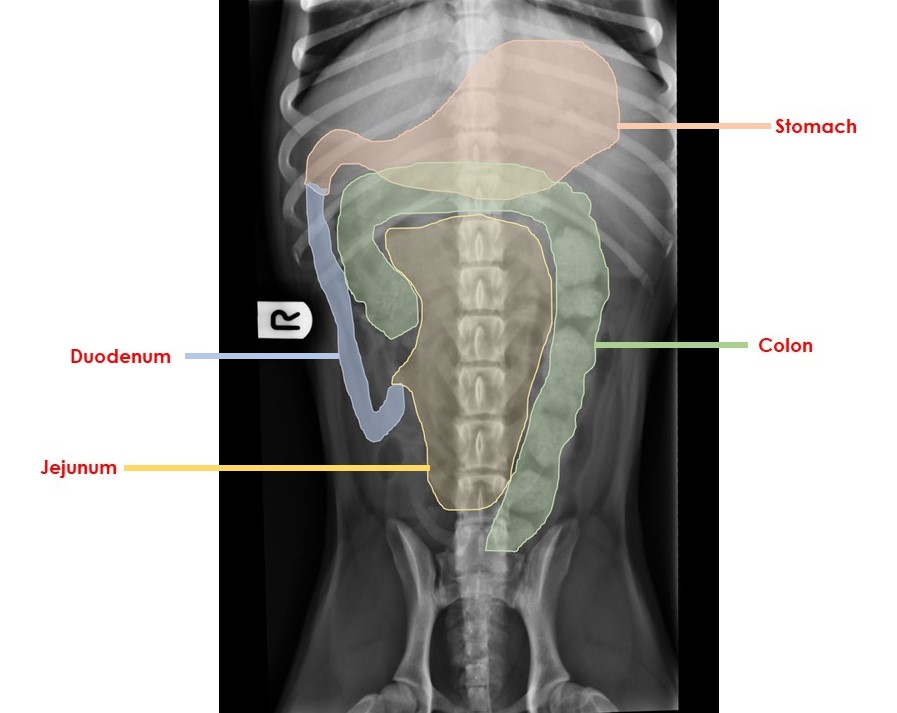

Dorsal, left or right lateral recumbency can be utilised and all confer different advantages. Dorsal recumbency is likely to allow complete visualisation of the gastrointestinal tract, whilst lateral recumbency (left or right) will assist with redistribution of luminal gas or fluid, thus allowing more compete visualisation of individual sections of the GI tract (Figure 1). In deep chested dogs, an intercostal right lateral view may be required to visualise the proximal duodenum and/or gastric pylorus.

Figure 1. This ventrodorsal abdominal radiograph has been annotated to give a schematic representation of the position and course of parts of the GI tract in a dog. In cats, the stomach is orientated more obliquely, and the pylorus and duodenum are positioned closer to the midline.